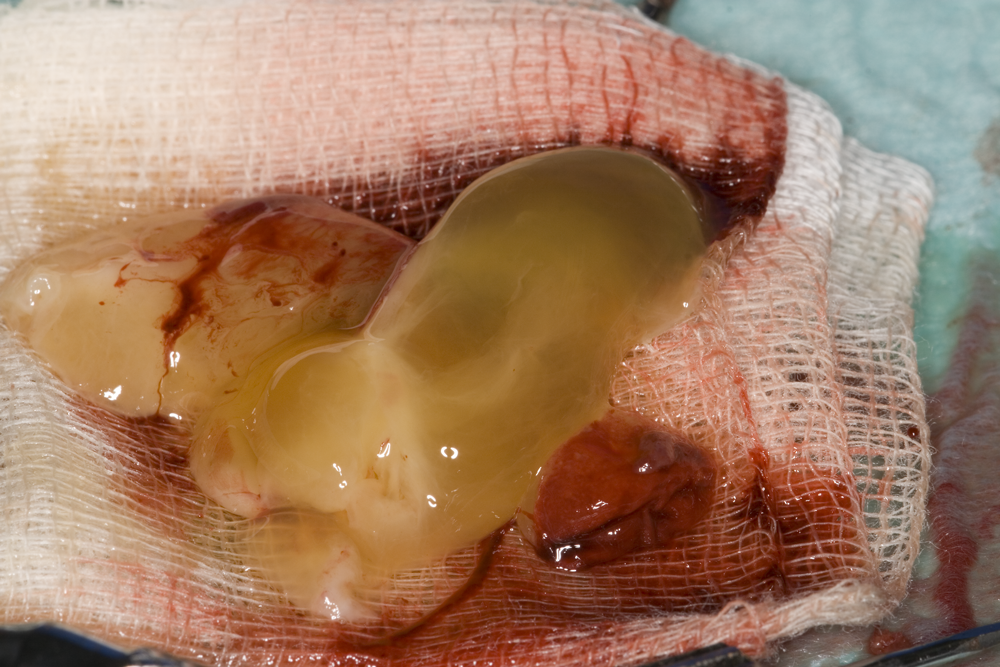

Автогенна кост

PRF